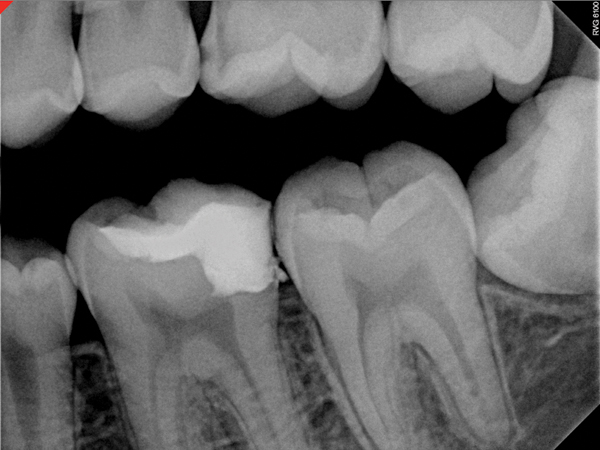

Figure 4. AND Figure 5. Before and after radiographs of bioceramic sealer hydraulically moved with the gutta-percha point. Note that the cold hydraulic technique results in lateral canal “puffs” similar to the warm vertical technique. Courtesy of Dr. Mohammed A. Alharbi.

Figure 4

Figure 5

Pre-mixed BC Sealer is the only pure medical-grade bioceramic product available as a sealer for endodontic obturation. It has the same basic chemical composition as the other pre-mixed bioceramic products, but it is less viscous, which makes its consistency ideal for sealing root canals. It is used with a gutta-percha point, which is impregnated on the surface with a nano particle layer of bioceramic. The gutta-percha is used primarily as the delivery device (plugger) (Figure 1 through Figure 3) to allow hydraulic movement of the sealer into the irregularities of the root canal and accessory canals (Figure 4 and Figure 5).